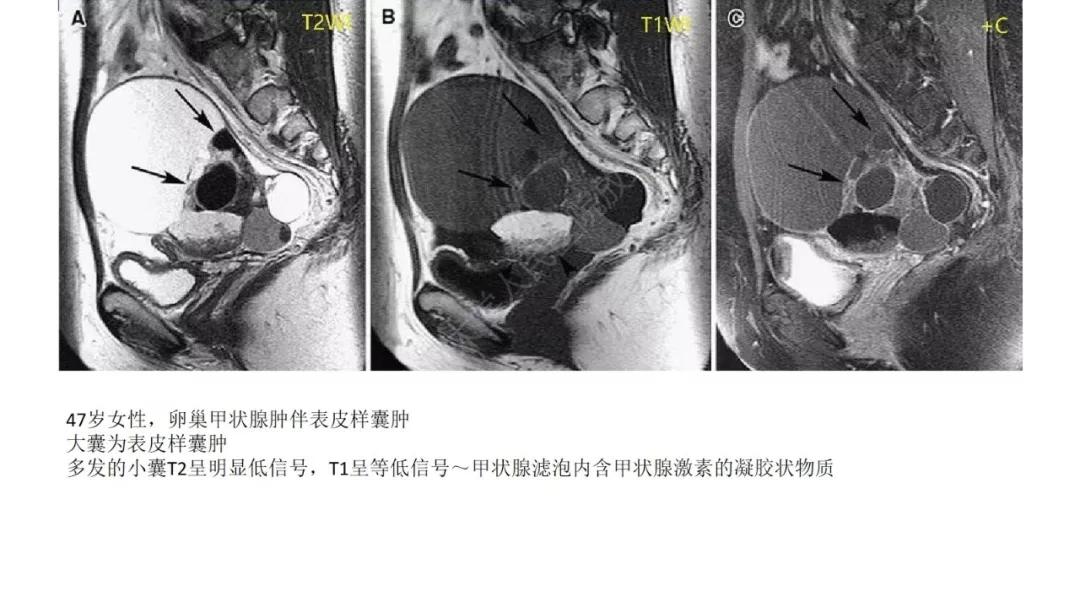

T2WI 低信号病灶:出血、平滑肌、纤维组织、卵巢甲状腺肿(凝胶)